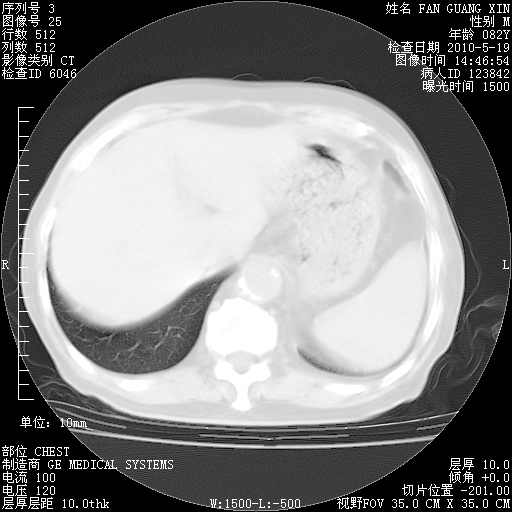

可改为口服强的松40-50mg/d治疗,若病情仍稳定,胸部阴影不再吸收可逐渐减量